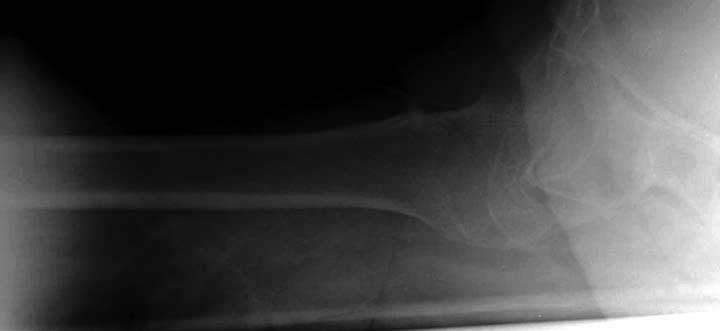

Сеньоры-пэры ревизировали гвоздем, шуруп поставили по той же дорожке, только поглубже. Да еще и bone graft не пожалели. "Результат" уже был через 2 дня.

Если сохранять головку - думаю надо было в валгусе фиксировать перелом гвоздем, или DCS, т.к. все-равно разрезали, чтоб достать DHS.

Вторая операция- это фаза сохранения головки бедра. Желательно приложить все усилия и сохранить головку, но, как видно, “фиаско” продолжается. Здесь вместо нейтрализации сил между медиальной и латеральными сторонами была попытка удержать варус. Варус не удержать ни деротационными шурупами о котором говорили и не костными стружками вбитые в шейку, потому что вся нагрузка упирается в головку.

Как отметил Евгений, 95 degree Blade Plate Fixed Angle device расчитана на восстановление взаимоотношении между головкой и диафизом, а все остальные фиксаторы (Gamma, Afifuxus и др.) работают за счет нагрузки в верхнем полюсе головки. Верхний полюс успели разрушить, и в головке единственное место, который смог бы удержать широкий клинок конструкции, это медиально-низкий сегмент. После установки клинка засчет дистракции можно удлинить конечность на 15мм, а добавленный в дефект ауто-графт закончил бы дело.

Третья операция-продолжения усилии “синьорами пэрами” по разрушению нормальной анатомии. Крест на головку! По видимому возраст позволяет биполярную конструкции, и при дефекте calcar пошли на обычный цементный. Ягодичные мышцы потеряли связь с вертелом, т.е. отсутствует верхний удержатель, и результат “a Big Screw Up!” Снимки вызывают головокружение!